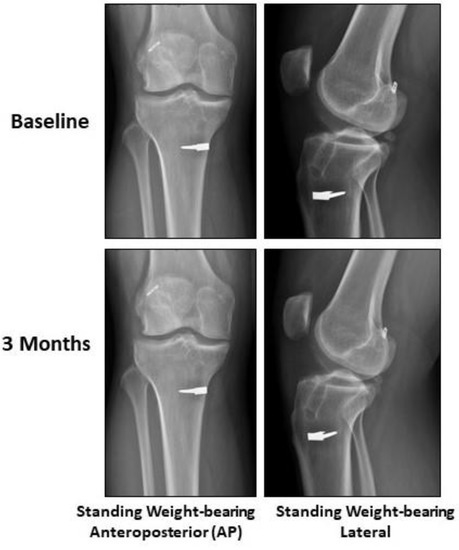

2.2. Case Presentation